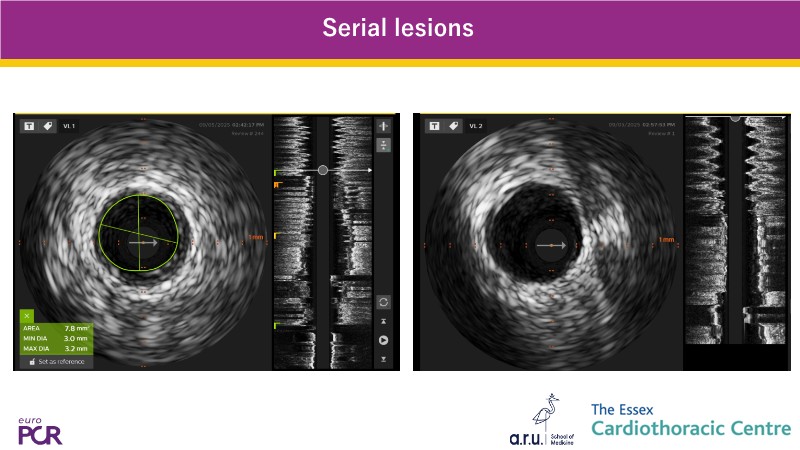

This EuroPCR 2025 session highlights how CathWorks FFRangio is reshaping coronary physiology assessment worldwide. Through case-based experience and real-world data, it showcases the integration of FFRangio into routine clinical workflows—from early adoption at Clinique Pasteur in Toulouse to implementation across the UK. The session also presents the growing body of diagnostic and clinical outcome evidence, along with a look at how FFRangio is evolving toward becoming a new standard of care in the cathlab.